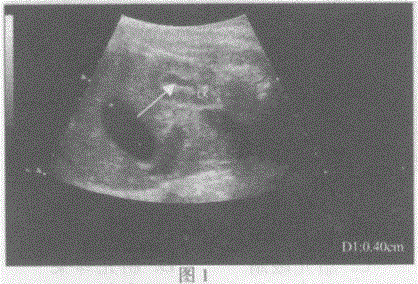

问题 临床资料:女,37岁,孕28周。 超声综合描述:胎儿腹部切面扫查,图1箭头所指宽度0.4cm形态不规则无回声,图2箭头所指宽度0.48cm形态不规则无回声,是指胎儿哪一部位异常: 超声提示:

选项 A.胎儿双肾重度积水 B.胎儿双肾集合系统分离 C.胎儿双肾囊肿 D.胎儿十二指肠闭锁(双泡征)

答案 B